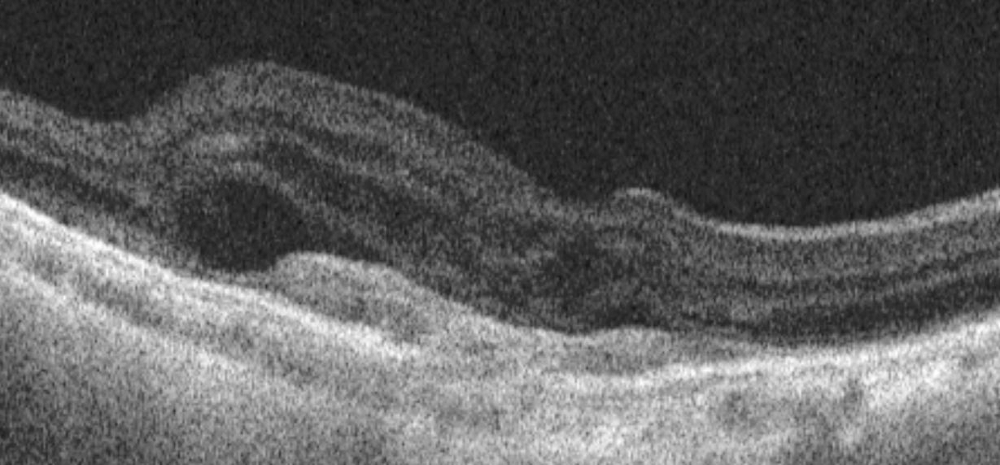

[Figure caption and citation for the preceding image starts]: Optical coherence tomography image showing subretinal hyper-reflective lesion, and subretinal and intraretinal fluidFrom the collection of Sajjad Mahmood MA, MB BCHIR, FRCOphth; used with permission [Citation ends].